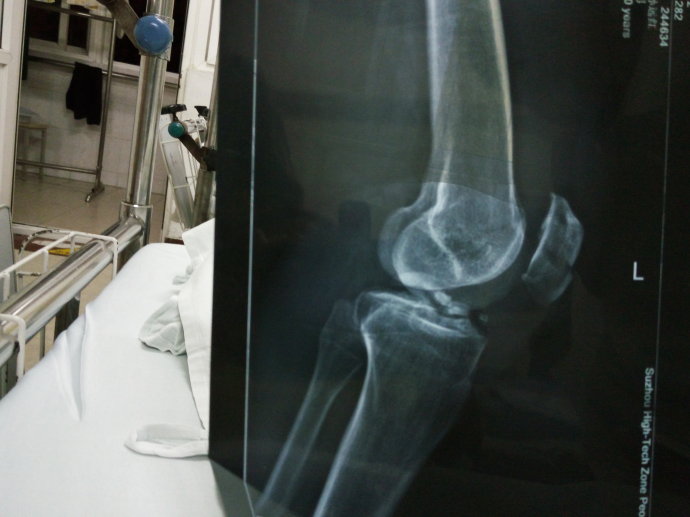

2015年5月14日星期四,在苏州工地打工的四川达州小伙子林成银骑电瓶车,不小心撞到了同样在苏州工地上干活,来自湖南新邵的孙运红。撞完后孙运红的左腿就不能动,经医院拍片检查:结果为左侧髌骨骨皮质横向断裂,见线性透亮线,左侧胫骨髁间突骨皮质断裂,边界硬化,并见小骨片游离;关节间隙未见明显狭窄,周围软组织肿胀明显。诊断意见:左侧髌骨骨折。

左腿上的碎片很明显,成游离状,骨裂部分已经红肿,发炎。